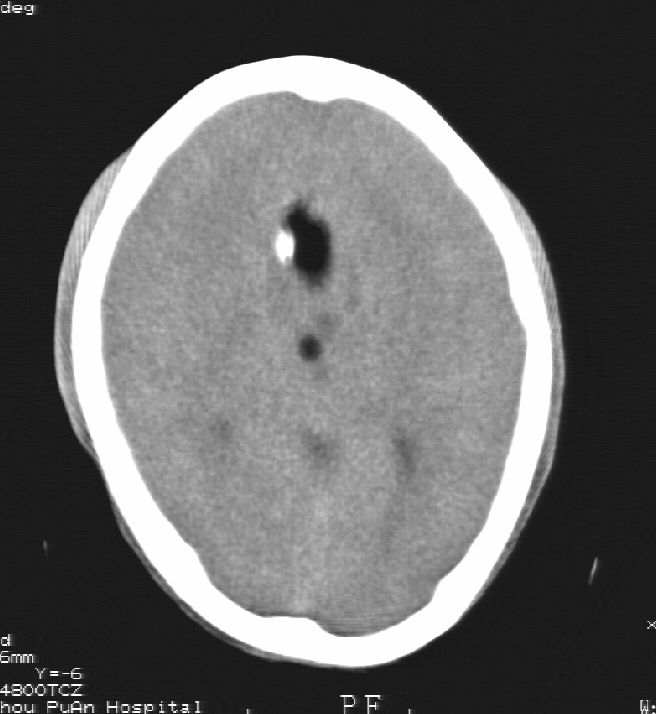

患者男,22岁,因外伤入院,低密度影ct值约-120hu。

胼胝体发育不全合并 透明隔缺如 、脂肪瘤。

胼胝体发育不全合并脂肪瘤;建议必要时行mri检查。

脑水肿,头皮下血肿,胼胝体发育不全、合并脂肪瘤及钙化;建议必要时行mri检查。

胼胝体发育不全、合并脂肪瘤及钙化。